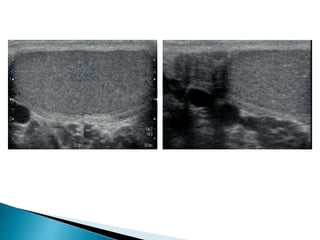

 In the acute stage ultrasound may be normal or

demonstrate a swollen testicle with patchy or

diffuse hypoechogenicity .

 The epididymis may also become swollen and

echo-poor.

 There may be a reactive hydrocele and the

overlying scrotal skin may be thickened and

oedematous.